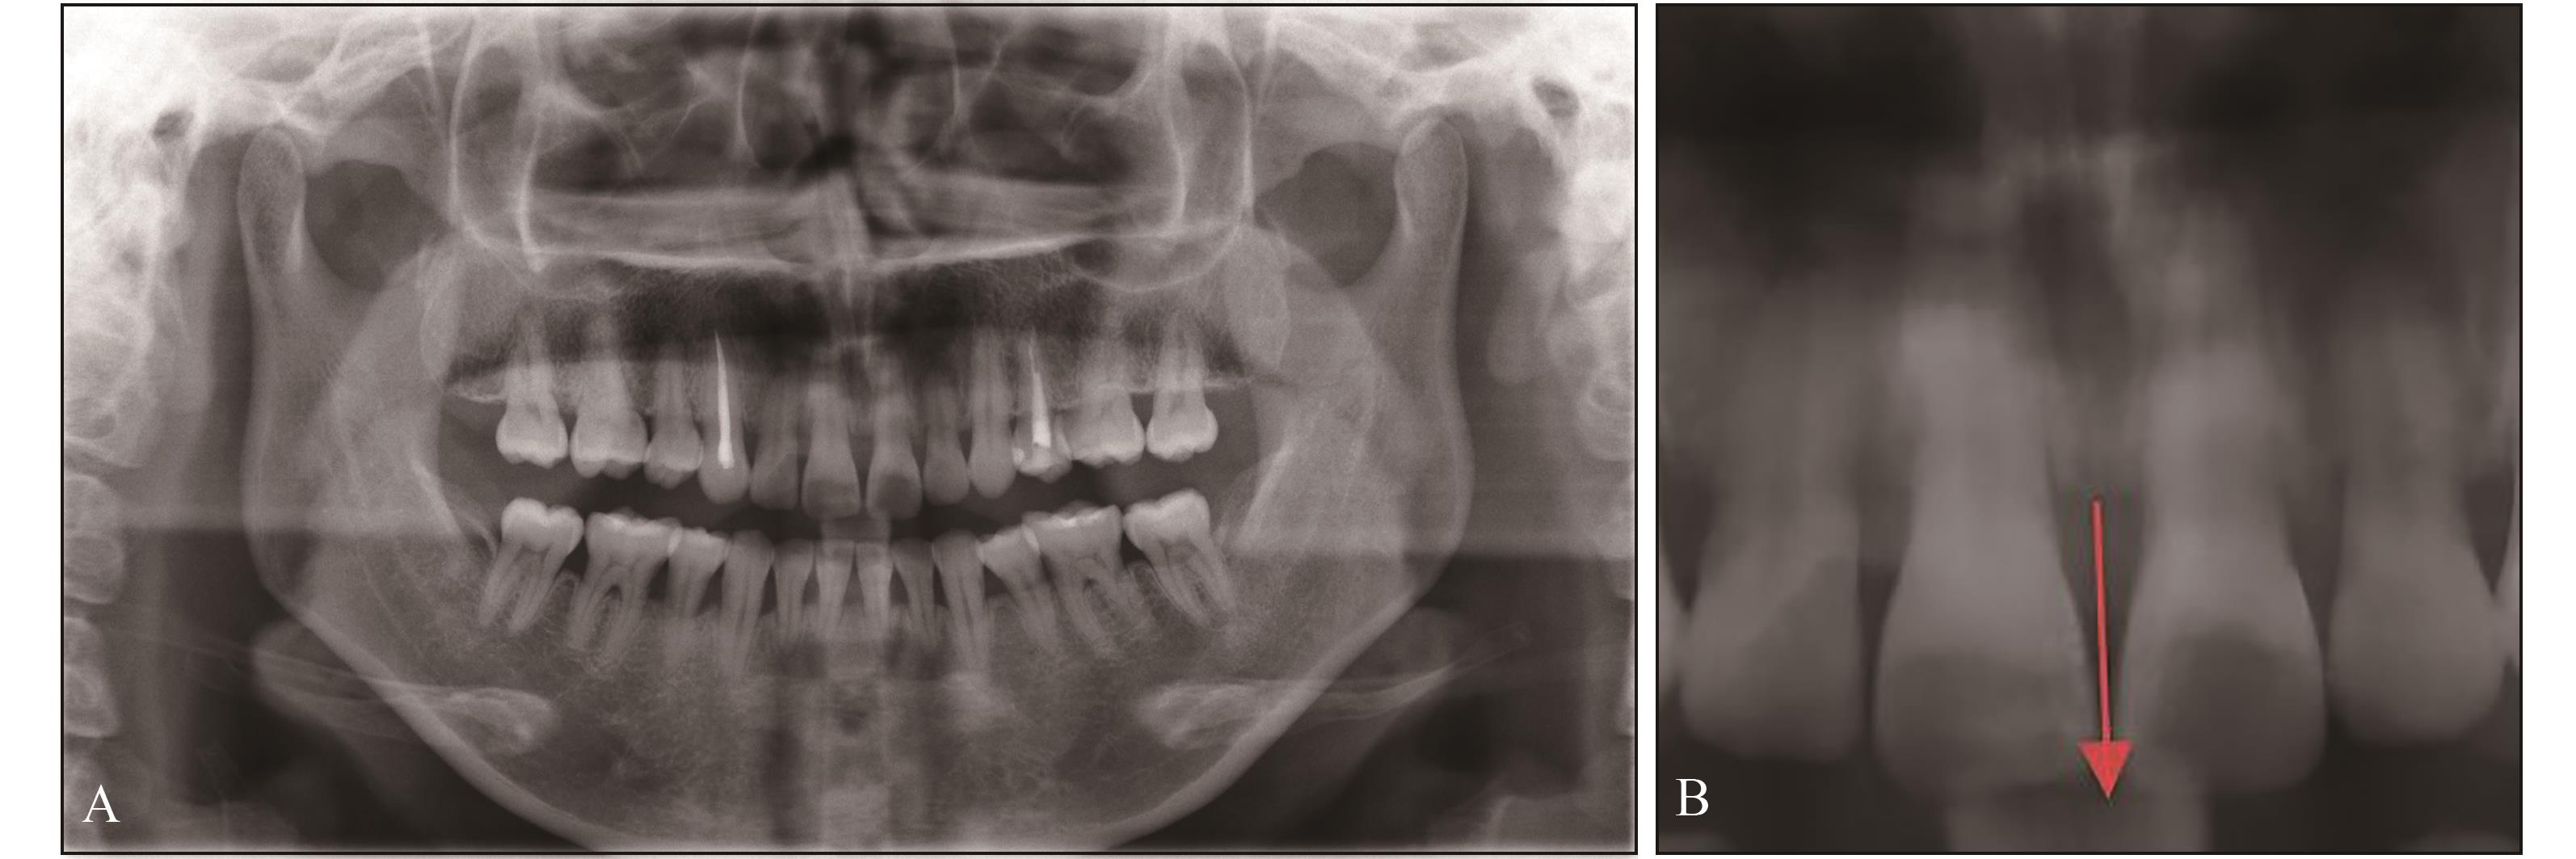

图 2

术前上前牙正面观"

图 3

术前X线片检查A:全景片;B:箭头示11、21牙槽嵴顶至21牙切端垂直距离约12.36 mm。"